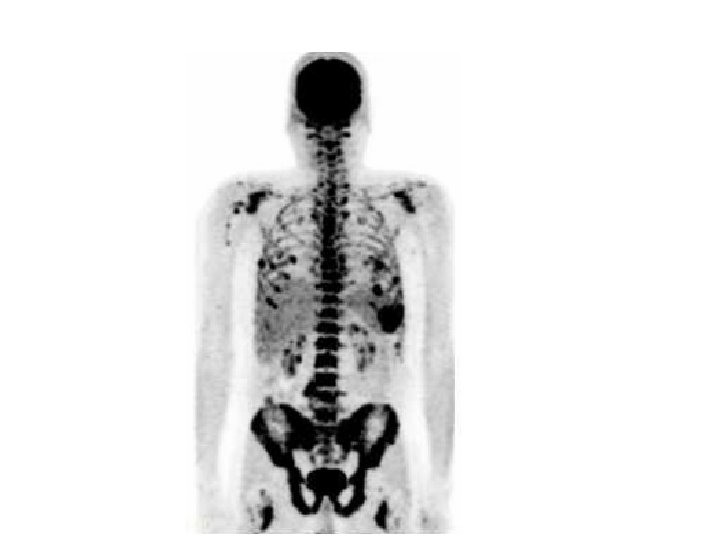

Myeloma • Multiple myeloma is a cancer in which abnormal cells collect in the bone marrow and form tumors. Sometimes these abnormal cells (called myeloma cells) collect in only one bone and form a single tumor known as a plasmacytoma. However, in most cases, the myeloma cells collect in many bones, forming several tumors and causing other problems. When this happens, the disease is called multiple myeloma.

Leukemia • Leukemia is cancer of the blood cells. It starts in the bone marrow, the soft tissue inside most bones. Bone marrow is where blood cells are made. When you are healthy, your bone marrow makes: ・White blood cells, which help your body fight infection. ・Red blood cells, which carry oxygen to all parts of your body. ・ Platelets, which help your blood clot. When you have leukemia, the bone marrow starts to make a lot of abnormal white blood cells, called leukemia cells. They don't do the work of normal white blood cells, they grow faster than normal cells, and they don't stop growing when they should.

Bone Marrow Biopsy